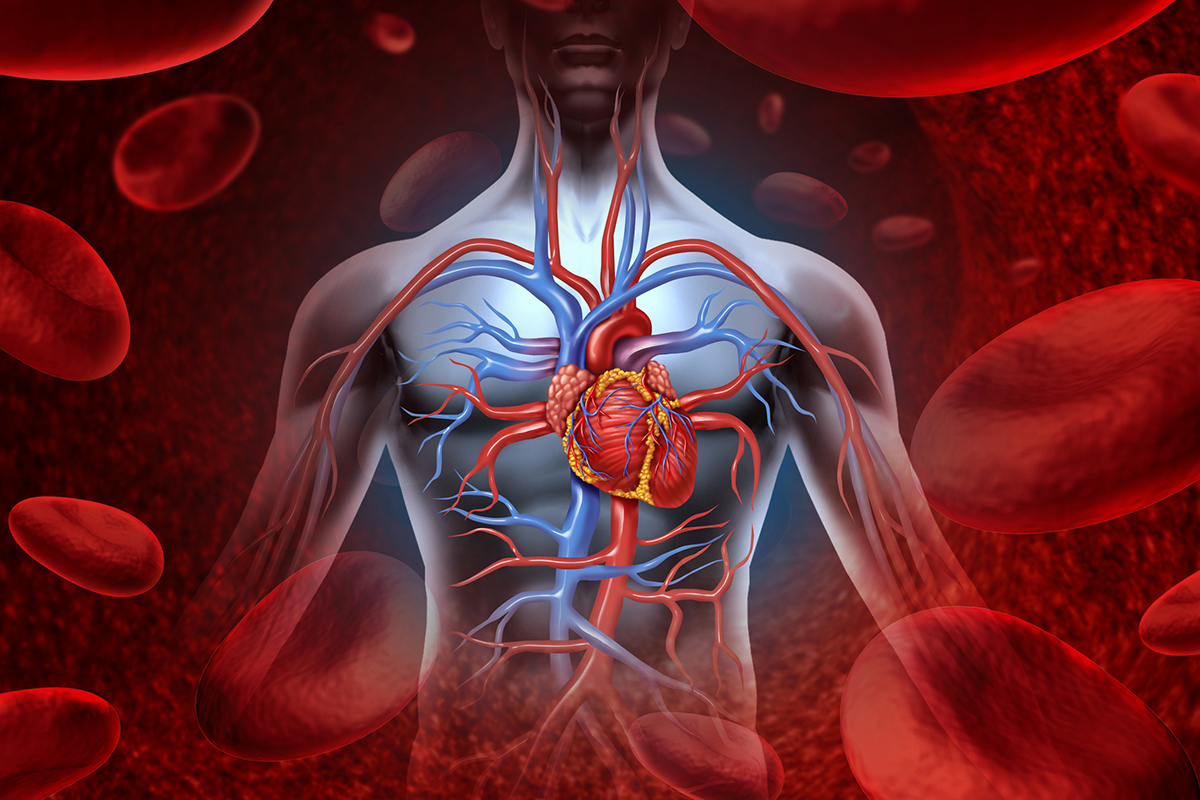

Анатомия здорового сердца: фотографии и иллюстрации